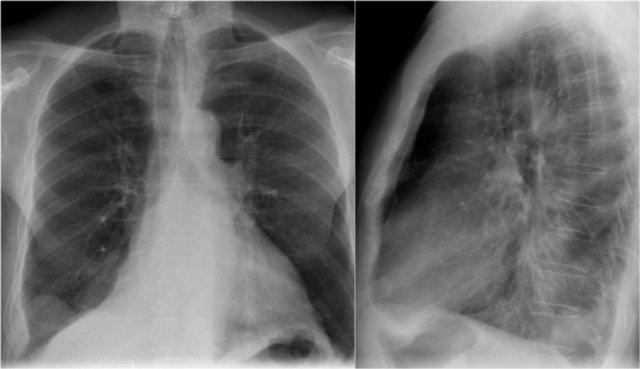

Hãy quan sát kỹ các hình X-quang trước, sau đó tiếp tục đọc.

Các dấu hiệu là gì và dấu hiệu nào được thấy ở đây?

Có hình ảnh xẹp thùy trên phổi trái.

Thông thường người ta không kỳ vọng vùng đỉnh phổi lại sáng như vậy, nhưng thực ra điều này là do ứ khí bù trừ của thùy dưới, khiến phân thùy đỉnh lan lên tận vùng đỉnh phổi.

Đây được gọi là dấu hiệu liềm khí (luft sichel sign).

Luft sichel có nghĩa là liềm khí (mũi tên xanh dương).

Lưu ý hình ảnh phồng của khe liên thùy trên phim nghiêng.

Điều này tương tự như dấu hiệu chữ S vàng (golden-S sign) trong xẹp thùy trên phổi phải và gợi ý có khối gây tắc nghẽn ở vị trí trung tâm.